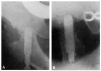

Fracaso número 4(observación número 21). Josefa T., setenta años. Afecta de síntomas de reblandecimiento cerebral. Dos meses antes de producirse la fractura, en un intervalo de quince días, tuvimos que extraerle por dos veces una cánula de lavativa de su ampolla rectal. La fractura fue tratada con el clavo de Sven Johansson (fig. 6. A y B), según la técnica habitual. A los veinte días de la intervención tuvo que pasar a su domicilio ante las quejas de los enfermos de las habitaciones próximas. La enferma estaba en una agitación constante y se quejaba continuamente. En su domicilio, donde la vigilancia no era tan severa como la de la clínica, abandonaba el lecho con frecuencia. Al mes y medio de la intervención notaron los familiares que la enferma, a pesar de su agitación, permanecía siempre en el lecho. Explorada entonces por nosotros, después de haber transcurrido una semana sin haberla visitado, comprobamos que el clavo hacía una prominencia bajo la piel, que estaba a punto de ser perforada.

Figura 6. A: obs. núm. 21. Radiografía practicada antes de la penetración completa del clavo, que en esta proyección está situado algo cranealmente. B: obs. núm. 21. Radiografía practicada antes de la penetración completa del clavo. La situación de éste es buena; con relación a la cabeza, es ligeramente ventral, debido a que la fractura no ha sido perfectamente reducida.

A pesar de que la situación del clavo no era ideal en este caso, no hay duda de que el resultado desfavorable obtenido fue condicionado por el estado mental de la enferma, la cual, o no hubiera tenido que ser operada, o, en todo caso, sometida, en el curso postoperatorio a una vigilancia más estricta.